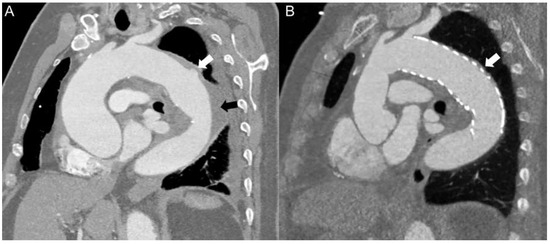

Veno-arterial extracorporeal membrane oxygenation (ECMO) is utilised as a short-term mechanical circulatory assist device for treatment of refractory acute cardiogenic shock. After a period of support, called “bridge to decision”, the options for ens...